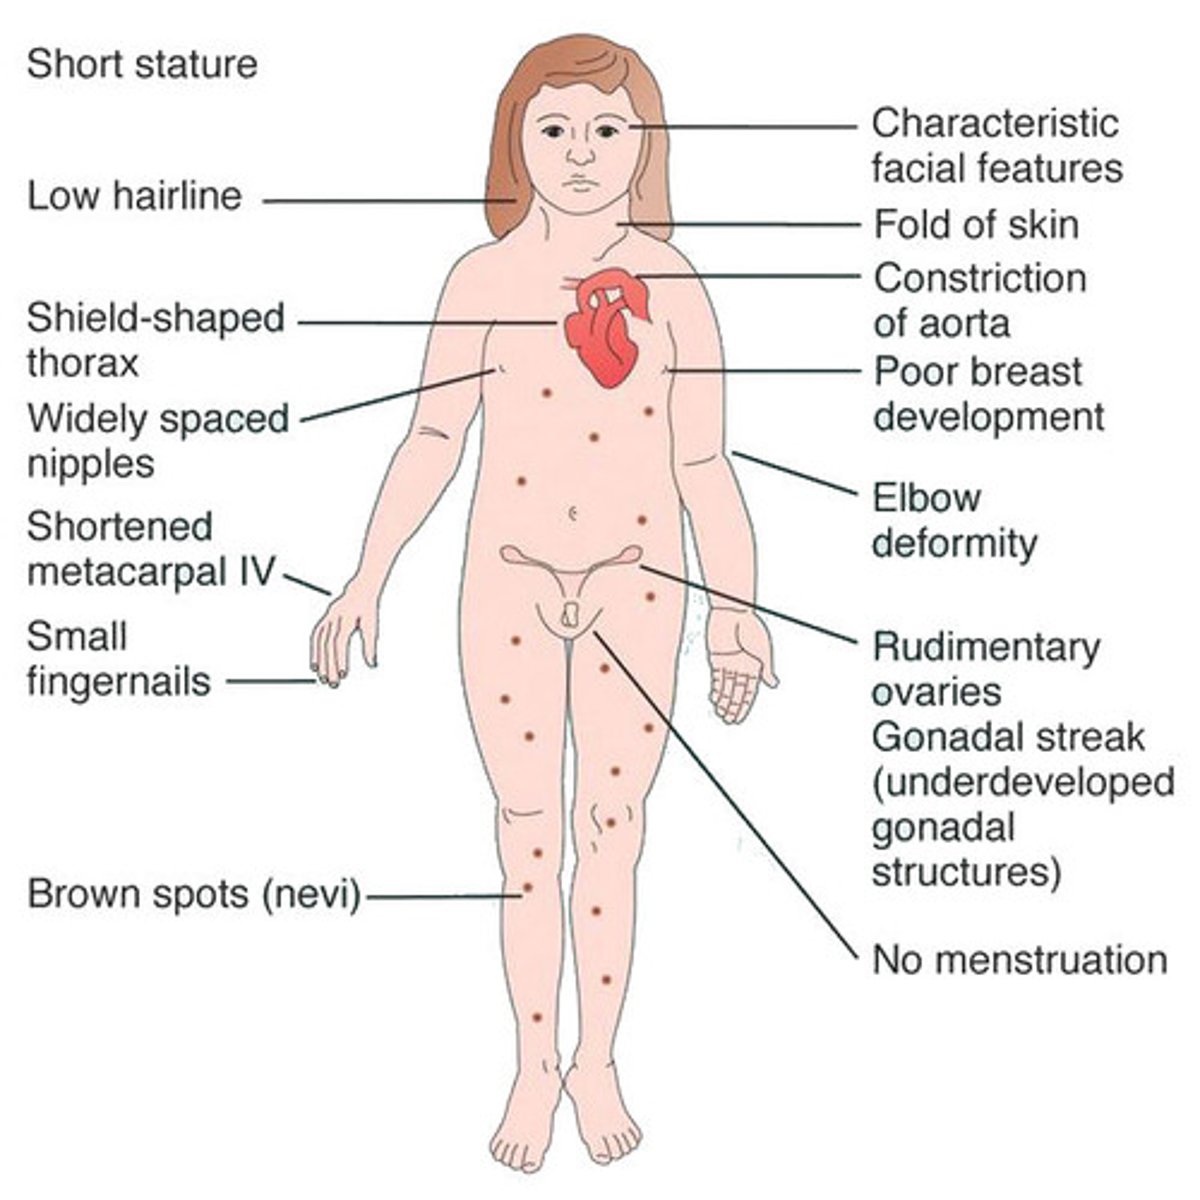

Streak ovaries, congenital heart disease (aortic dissection or bicuspid aortic valve), horseshoe kidney, cystic hygroma at birth, short stature, webbed neck, lymphedema

Turner Syndrome (45 X,O)